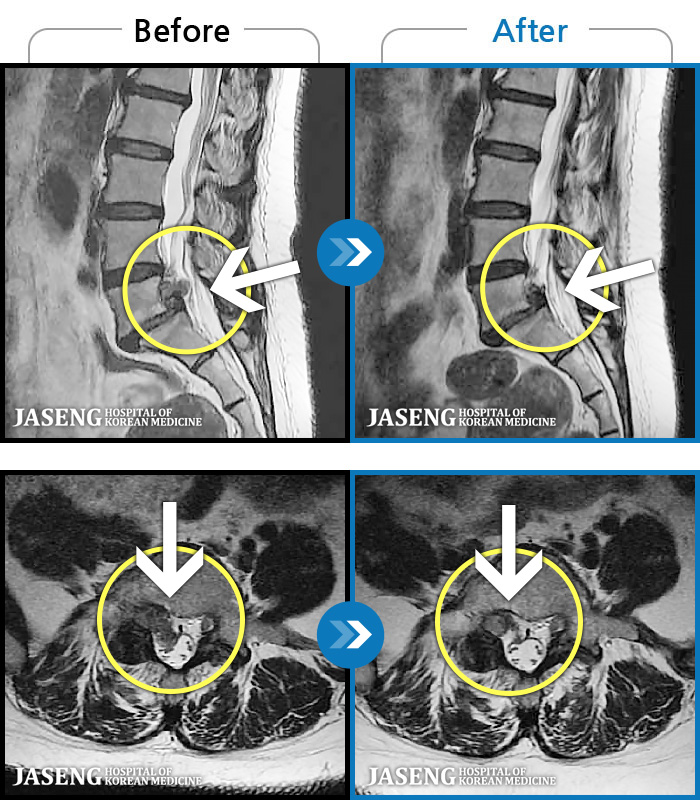

MRI ġ

1,237 MRI ũ ʸ Ȯϼ.

㸮 ϻ .